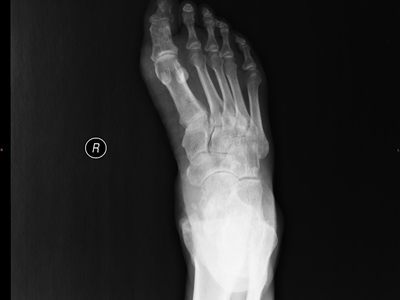

痛风是由于嘌呤代谢紊乱和尿酸排出减少,而引起的尿酸盐结晶沉积性病变,可累及指关节、第一跖趾关节、耳廓等处,造成急性炎症反应性滑膜炎。常于中老年发病,男性发病率明显高于女性,以皮下出现痛风石、痛风性关节炎、关节畸形、肾结石或肾脏病变为临床特征。痛风治疗原则为治疗高尿酸血症和控制关节炎。

痛风病程较长,常反复发作而迁延不愈形成痛风石,是痛风的特征性临床表现,常见于指关节、第一跖趾关节、耳廓等处。外观为隆起、大小不一的不规则的黄白色赘生物,表面菲薄,破溃后排出白色粉状或糊状尿酸盐结晶物,经久不愈,但较少继发感染。部分患者伴有肾结石及肾脏病变。